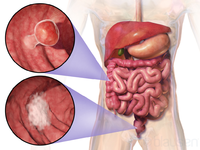

سرطان القولون والمستقيم

مقالة مفصلة: سرطان القولون والمستقيم

| سرطان القولون والمستقيم | ||

| معدل الانتشار | 9.4 مليون (2015)[7] | |

| معدل البقاء 5 سنوات | 65% (الولايات المتحدة)[4] | |

| حالات الوفاة | 832.000 (2015)[6] | |

| عوامل الخطورة | التاريخ العائلي لحدوث سرطان القولون والمستقيم في الأسرة؛ سلائل (پوليپات) polyps أو أمراض الأمعاء الالتهابية. تم ربط وجود طفرات جينية نوعية بداء السليلات الغدومي العائلي familial adenomatous polyposis (الذي يمكنه أن يتحول إلى سرطان القولون) وبسرطان القولون والمستقيم الوراثي غير السليلي. ويزداد خطر الإصابة أيضا عند الذين يعيشون في المدن أو المناطق الصناعية. وتتضمن بقية عوامل الخطورة نقص النشاط البدني والتعرض لمواد كيميائية معينة وتناول الأغذية الغنية بالدهون أو قليلة الألياف. | |

| العلامات المنذرة | وجود دم في البراز؛ أيُّ تغيرٍ في عادات التغوط؛ انزعاج معدي عام، فقدان وزن ليس له ما يبرره. | |

| الكشف والتشخيص | يجب إجراء فحص المستقيم بالإصبع وتحرّي الدم في البراز سنويا لكل شخص يفوق الأربعين عاما؛ تنظير السيني sigmoidoscopy كل 3 ـ 5 سنوات بعد سن الخمسين. وإذا اشتُبِه بوجود أي اضطرابات، يمكن إجراء تنظير القولون واستخدام رحضة (حقنة) الباريوم barium enema (للتمكن من رؤية الأمعاء عند التصوير بالأشعة السينية). ويكون الإنذار prognosis سيئا إذا كانت الأمعاء مسدودة أو مثقوبة أو كانت مستويات مواد واسمة marker substances معينة (مثل المستضد الجنيني السرطاني carcinoembryonic antigen والمستضد الكربوهيدراتي 9-19) في مصل الدم مرتفعة قبل العلاج.

| |

| العلاج | الجراحة لإزالة الورم، وأحيانا يضاف إليها المعالجة الشعاعية أو الكيميائية أو كلتيهما. وقد يتحتم في بعض الحالات فَغْر القولون colostomy (عمل فتحة تصريف فيه). وإذا انتشر المرض إلى العقد اللمفاوية، تصبح المعالجة الكيميائية بالفلوروراسيل fluorouracil مفيدة. وبالنسبة لسرطان المستقيم المتقدم والمتوسط الشدة تستخدم المعالجة الكيميائية المترافقة مع المعالجة الشعاعية، ولعل إزالة النقائل من الكبد جراحيا تطيل بُقيا بعض المرضى.

| ملاحظات | ||